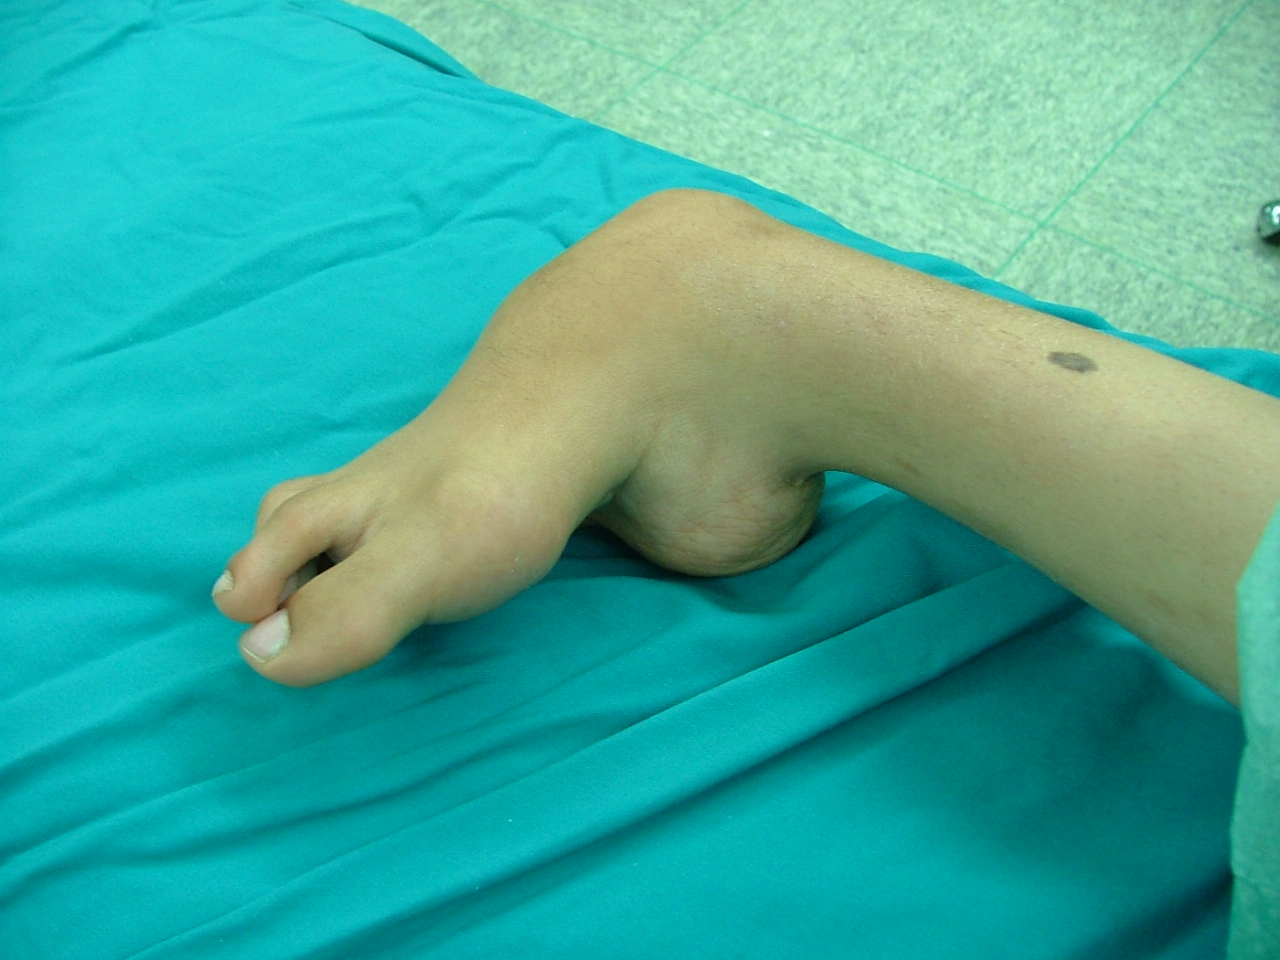

این عمل در مرکز جراحی ولنجک و زیر نظر دکتر حقانی فوق تخصص دست صورت گرفته

تاریخ عمل  پنج شنبه 20 شهریور 1393

شست کوتاه